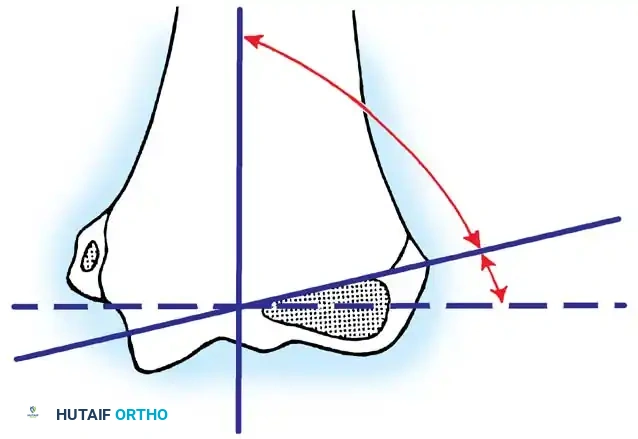

Fig. 33-42 Reduction technique for radial neck fractures.

- Positioning: The patient is placed supine. An assistant firmly stabilizes the distal humerus and the radius distal to the fracture site.

- Maneuver: With the elbow in full extension, the surgeon applies a strong varus stress to the elbow with one hand. This opens the radiocapitellar joint laterally.

- Reduction: Using the thumb of the opposite hand, direct lateral-to-medial pressure is applied over the tilted radial head to lever it back into anatomical alignment.

- Immobilization: The forearm is then placed in 90 degrees of flexion and pronation to lock the reduction.

Fig. 33-45 Mechanism of reduction of radial neck fracture.